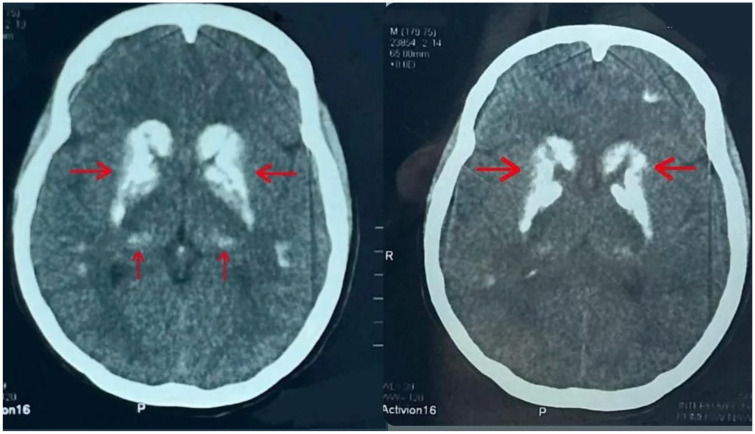

Fahr Syndrome or Strio-Pallido Dentate Calcinosis is a rare neurological syndrome characterized by deposition of calcium in basal ganglia, which usually occurs secondary to other underlying endocrinological disorders like hypo/hyper-parathyroidism. Symptoms vary greatly and may range from psychiatric ones like confusion and hallucination to neurological like Tremors, Rigidity, with seizures being the rarest manifestation. Laboratory tests and brain imaging play a crucial role in establishing the diagnosis, while treatment primarily focuses on managing symptoms. Here, we report a case of a 17-year-old female diagnosed with Fahr's syndrome secondary to hypo-parathyroidism, onset of the disease at such young age coupled with uncommon presentation of fits makes this case rather remarkable.

Abstract Image